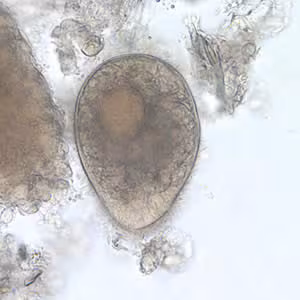

A group of refugees from Southeast Asia were being screened for parasites as part of a medical evaluation. Stool specimens were collected and processed. Examination of a wet mount from a formalin-ethyl acetate (FEA) concentration of one individual’s specimen revealed the object seen in Figure A. The objects were seen in low numbers and measured approximately 75 µm in length. What is your diagnosis? Based on what criteria?

Figure A